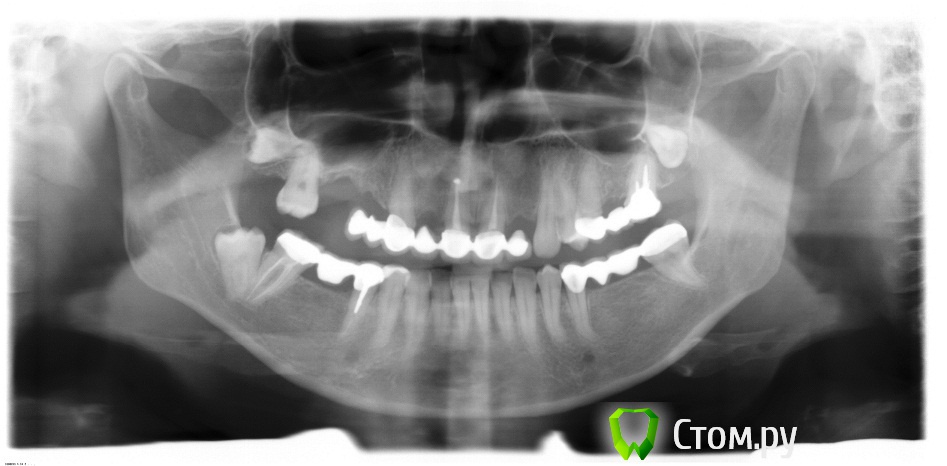

inostranka Опубликовано 9 марта, 2014 Поделиться Опубликовано 9 марта, 2014 Добрый день,уважаемые стоматологи! Меня зовут Светлана,мне 37 лет.Наконец-то появилась возможность поставить импланты.Посоветуйте план лечения,пожалуйста.К своему доктору я попаду только 24 апреля,а снимок мне уже прислали.Выкладываю его здесь.Заранее спасибо. Ссылка на комментарий

Afffinity Опубликовано 9 марта, 2014 Поделиться Опубликовано 9 марта, 2014 (изменено) На верхней челюсти вам грозит синус-лифтинг (справа), без него никак. С остальным проблем думаю не будет. Плюс удалить все восьмерки (зубы мудрости). Изменено 9 марта, 2014 пользователем Afffinity Ссылка на комментарий

inostranka Опубликовано 9 марта, 2014 Автор Поделиться Опубликовано 9 марта, 2014 Спасибо.Про синус мне говорил доктор,а по поводу восьмёрок говорил,что они лежат в десне и не мешают,а одна из них опорой моста является. Ссылка на комментарий

Bier Опубликовано 9 марта, 2014 Поделиться Опубликовано 9 марта, 2014 справа внизу - однозначно удалять восьмерку. справа наверху - объем вмешательства сильно зависит от эстетических требований и линии улыбки. 1 Ссылка на комментарий

inostranka Опубликовано 9 марта, 2014 Автор Поделиться Опубликовано 9 марта, 2014 Bier,спасибо за совет.Теперь у меня вопрос: возможно ли совместить удаление восьмёрок,синус-лифтинг и имплантацию? И сколько тогда имплантов придётся ставить? Ссылка на комментарий